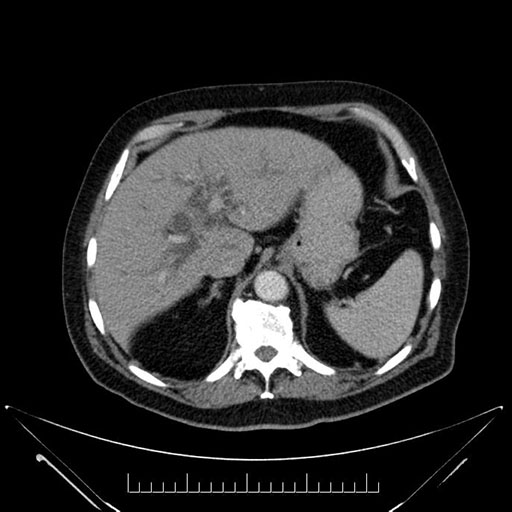

Imaging Analysis

Look through the patient's CT scan to identify any areas of concern for the necessary procedure.

Based on your CT findings, which issue(s) would give reason for "planned slowing down moment(s)" in this case?